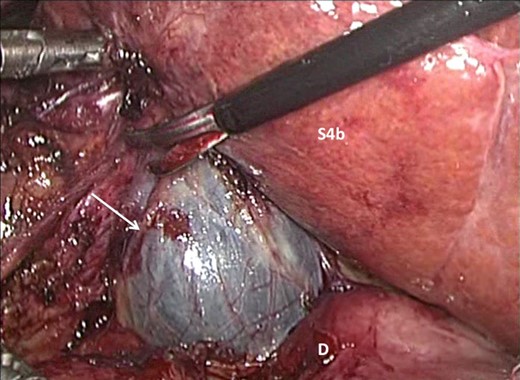

A laparoscopic completion cholecystectomy was performed. There were multiple dense adhesions that precluded visualization of the gallbladder remnant (Fig. 2). Meticulous dissection with cautery attached to ‘hot scissors’ eventually presented the gallbladder remnant (Fig. 3). Scarring at Calot's triangle prevented retrograde dissection, so the ‘dome down’ technique was used to identify cystic duct (CD) (Fig. 4) and right hepatic structures at the floor of an open-type Rouviere's sulcus (Fig. 5). Intraoperative cholangiography was performed via the CD using a 5Fr infant feeding (Fig. 6) and confirmed that: this structure was the CD, the extra-hepatic biliary tree was normal and there were no stones in the CBD (Fig. 7). At this point, the CD and artery were ligated and ‘hot scissors’ were used to separate the gallbladder remnant from the liver bed. This patient recovered uneventfully and remained asymptomatic 2 years later.

Careful dissection with ‘hot scissors’ has presented the ‘fundus’ of the gallbladder remnant (arrow). The duodenum (D) and segment IVb of the liver (s4b) are visible after dissection.